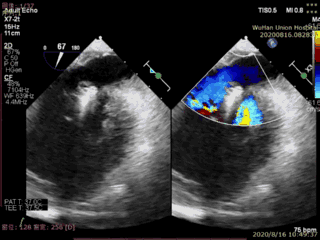

本例患者是一名高龄男性,合并多种疾病,术前超声心动图显示二尖瓣后叶P2脱垂、连枷伴重度二尖瓣反流。手术在食道超声引导下进行,植入1枚IIIs型二尖瓣夹合器,术后即刻显示二尖瓣反流消失,导管操作时间不到20分钟,手术取得圆满成功。

术前超声图